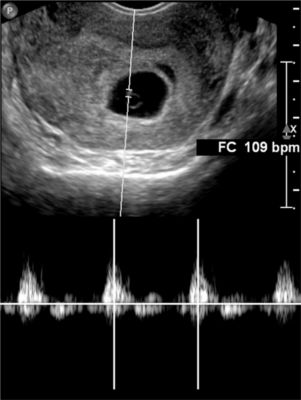

Echographie et Doppler

Echographie générale, echographie obstetricale, doppler veineux ou artériel, une techique simple mais qui demande une grande dextérité...